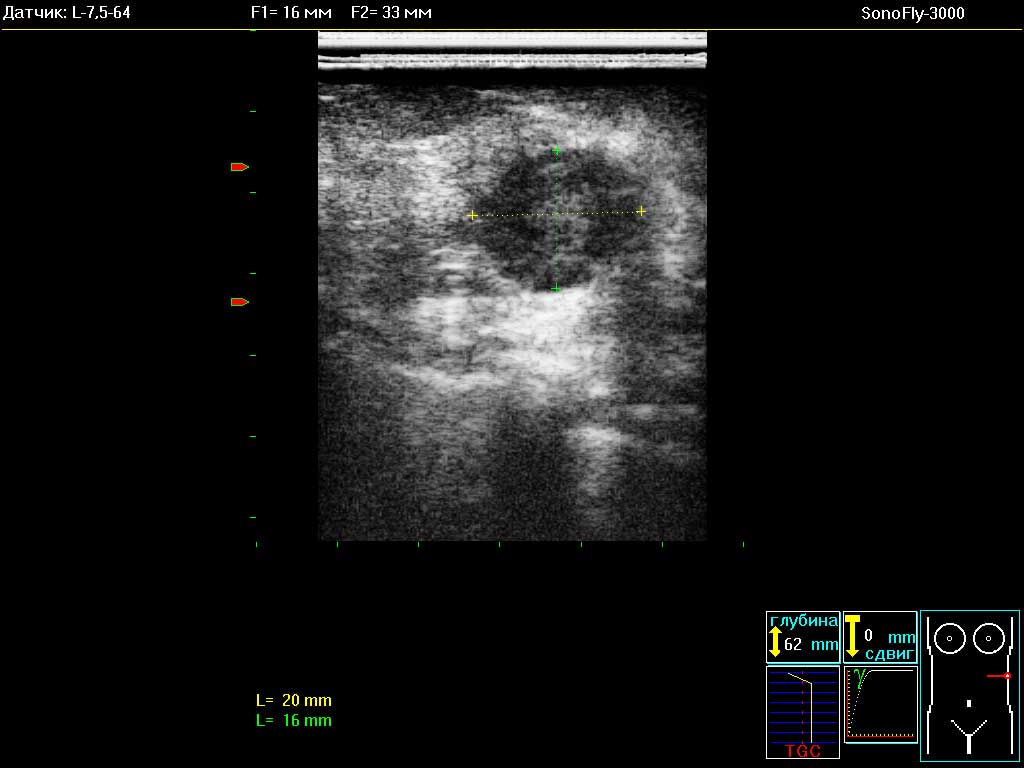

- Ультразвуковые УЗИ сканеры SonoFly